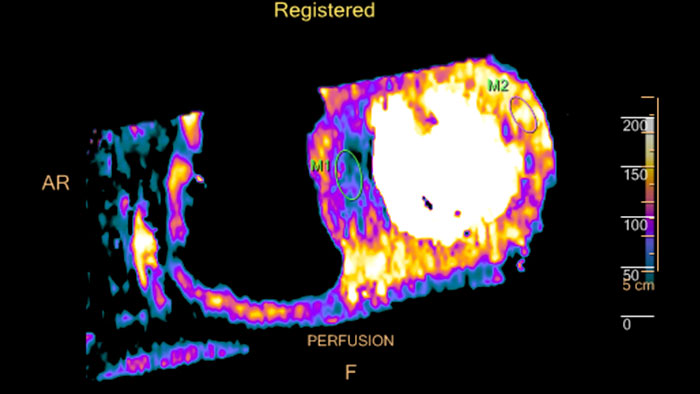

MI Fusion

CT-MI Fusion

Fusing cardiac CT-MI images

Cardiac CT-MI Fusion incorporates support for myocardial perfusion imaging (MPI).

ct mi fusion

Benefits

• Allows loading both gated and un-gated rest, and gated and

un-gated stress MI datasets simultaneously with the CT.

• The MI images are displayed in the short axis and the two long axis planes.

• The axes definition is derived from the CT study.